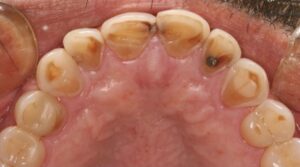

Soft drinks have many potential health problems. The inherent acids and sugars have both acidogenic and cariogenic potential, resulting in dental caries and potential enamel erosion.

Fizzy drinks contain large amounts of sugar and will, therefore, increase the risk of tooth decay. Both regular soft drinks and their diet alternatives contain acids that can erode the outer surface of the tooth.

When you drink fizzy drinks such as Coke, Sprite, Fanta or any energy drinks, the sugars in it interact with the bacteria in your mouth to form acid. This acid is what attacks your teeth and starts to form cavities and decay. Both regular fizzy drinks and ‘sugar-free’ soft drinks contain their own acids which both have their own way to attack your teeth. Sugar-free may be a slightly healthier version for you but it will still have similar effects on your teeth.